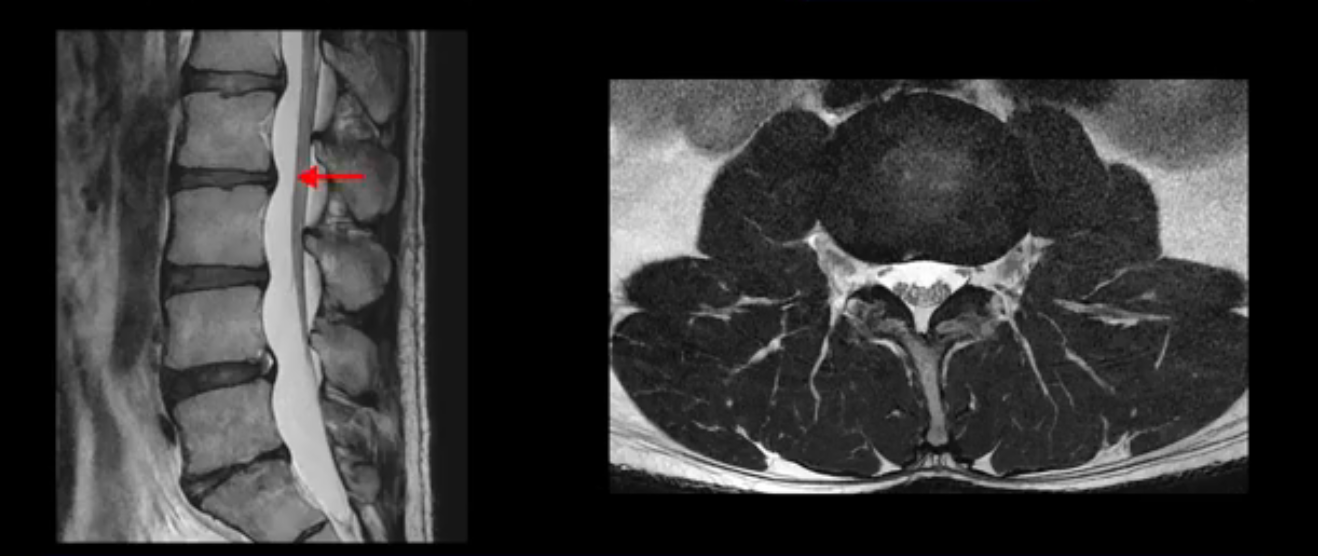

2번 3번도 비교적 디스크 상태는 좋고 신경 구멍 넓이도 아주 넓습니다.

3번 4번도 마찬가지로 디스크상태 좋아 보이고 신경 눌림 전혀 없어 보입니다.

추간공도 보시다시피 왼쪽, 오른쪽 전부 다 매우 넓어서 신경이 눌릴만한 부분이 전혀 보이지 않습니다.